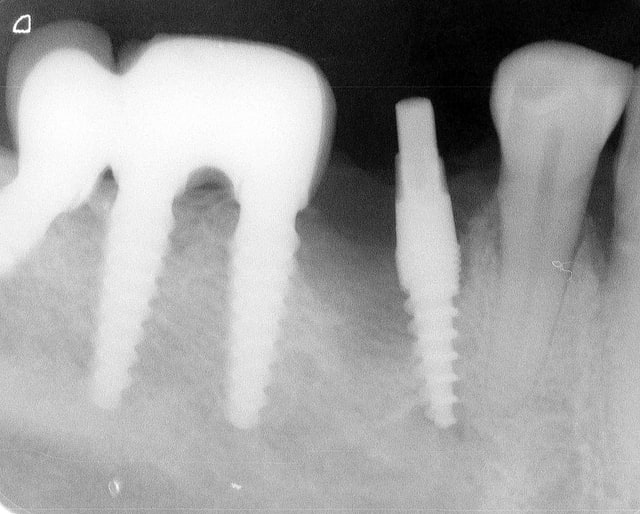

attention exces de ciment distal 36....

Il semblerait que ces excès causerait d'emblé des péri-implantites selopn les paro.

Oui ca semble ....sur la opg radio tu peux voir la situation seulement deux semaines après l´implantation immédiate 34 jusqu´à 36 et 45, les derniers 2 photos montrent la même situation après un an ( où on a enlevé la supra construction pour un contrôle). Sur ce cas je voulais montrer la bonne régénération osseuse et de la gencive.

le pilier distaL, EST-CE DE LA ZIRCONE SUR LE PILIER CIMENTÉ?

> le pilier distaL, EST-CE DE LA ZIRCONE SUR LE PILIER CIMENTÉ?

Oui,c´est un Prep cap zircone , que je cémente juste après l´implantation immédiate pour mieux former la gencive. Les implants monoblocs ont étés implantés entre 40 et 60 Ncm . Les photos 6 et 8 on voit les prep cap juste après l´implantation immédiate ce sont des sortes de "couronnes" pré fabriquées.